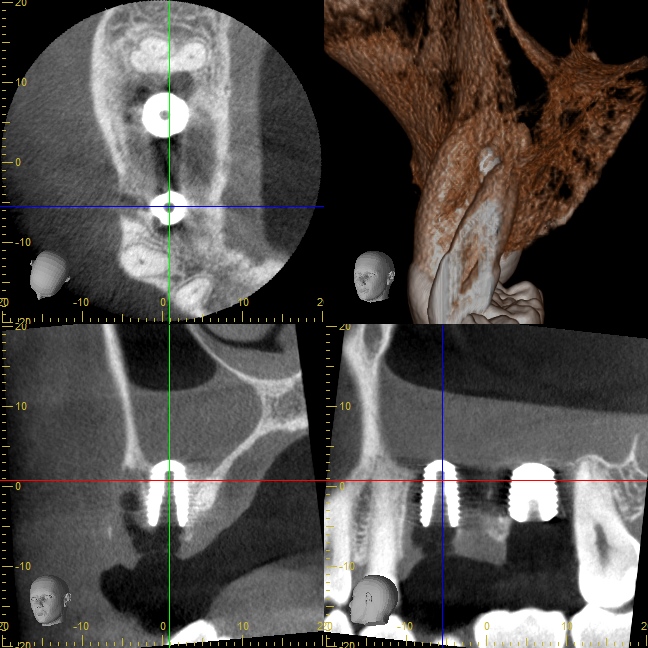

治療後のCT写真

インプラント周囲に健全な骨が再生されています。

上顎洞粘膜をDensah® Burでリフトアップした部分にも緻密な骨が再生されました。